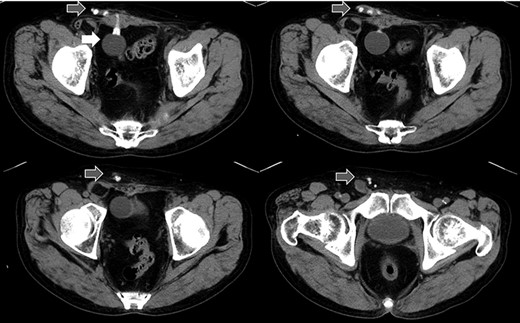

Abdominal CT in Case 1: CT showed that there was a balloon nearby the bladder and the tube went beside the rectus abdominis muscle from abdominal cavity; balloon, white arrow; tubes, gray arrows.

A 79-year-old male was referred to our institute for the treatment of right IH. He had received AUS implantation for the treatment of incontinence after RP for prostate cancer. Abdominal

computed tomography (CT) showed right IH and a balloon that was placed by the bladder and a connecting catheter that went through the lateral side of the rectus abdominis muscle (Fig. 2). In the operation, we performed ultrasonography (US) at first and it demonstrated that the catheter was running through the inguinal canal (Fig. 3). When we incised the aponeurosis of the external abdominal oblique muscle, the catheter of the AUS was observed in the inguinal canal (Fig. 4). We identified the hernia sac protruding from the inguinal ring and diagnosed it as an indirect IH. The adhesion was too hard to separate the catheter from the pubis and posterior wall of the inguinal canal around pubis. Then, the IH was repaired using the Lichtenstein technique; however, the mesh near the pubis could not be spread as ordinarily.